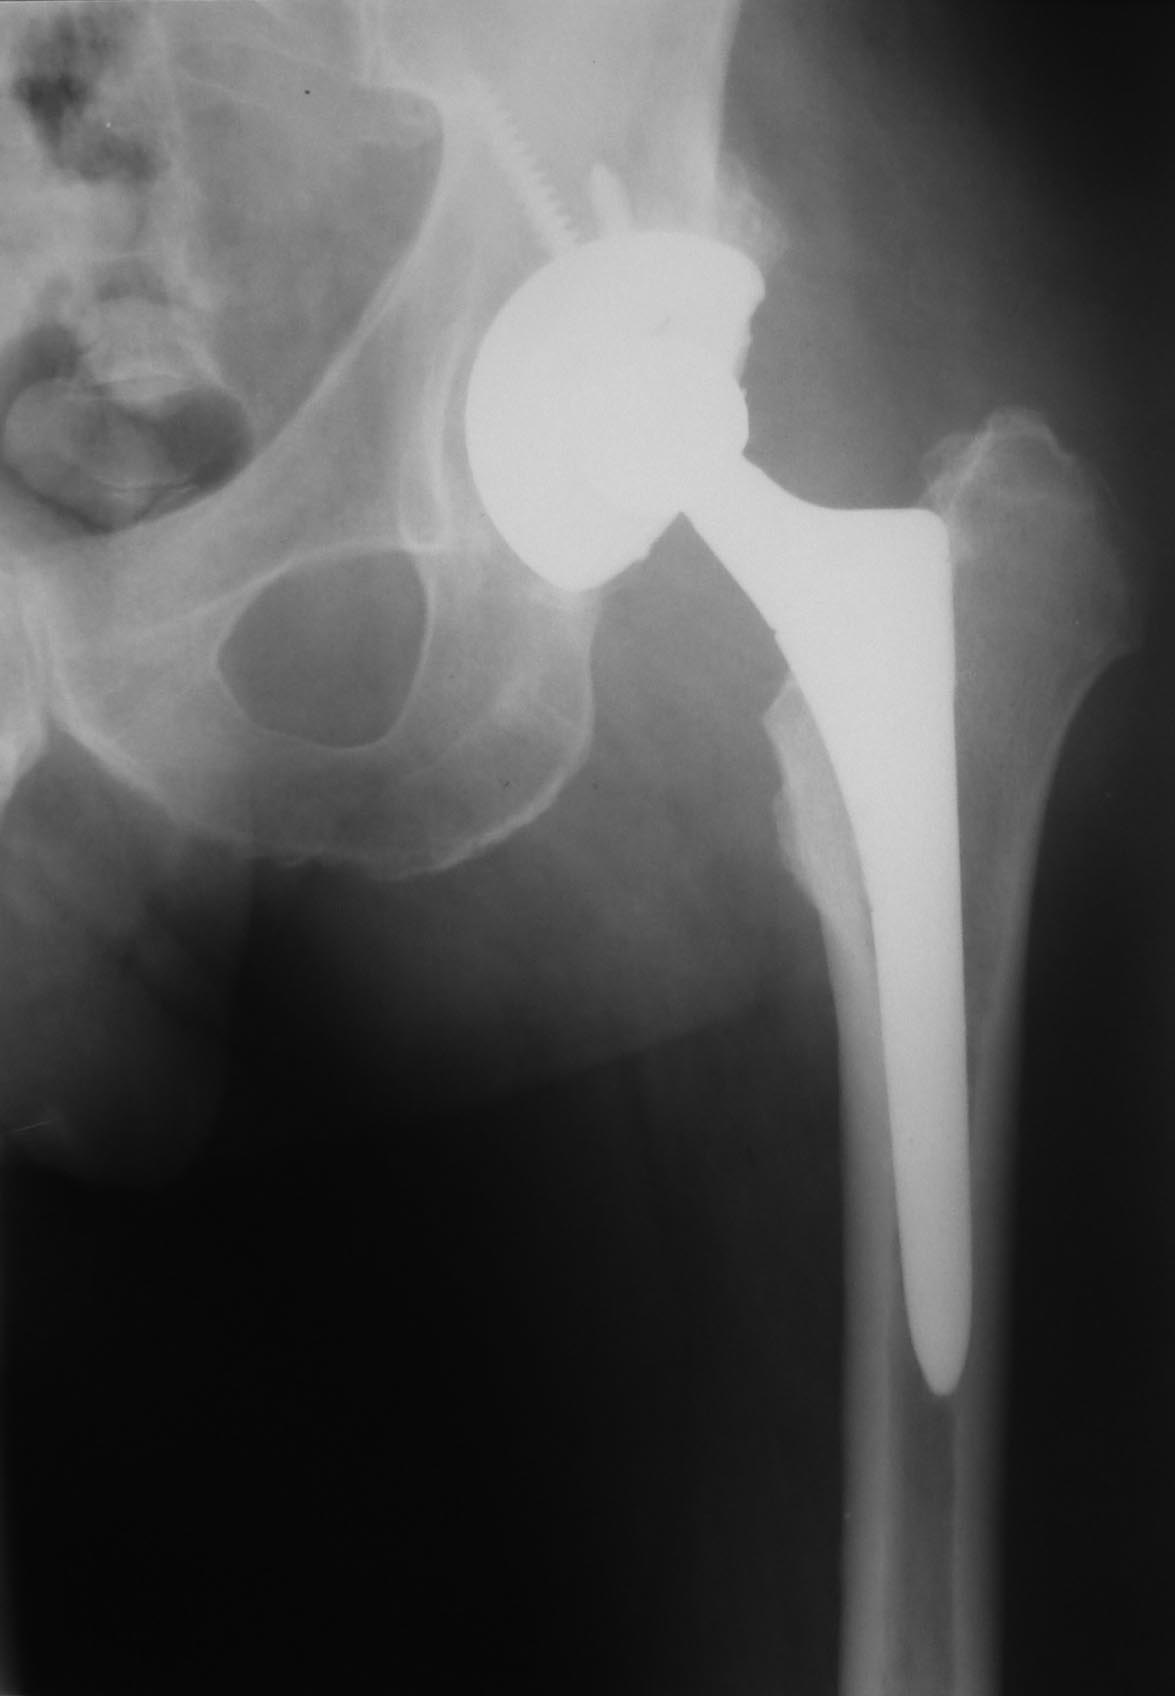

Пациент 55 лет. 6 лет после эндопротезирования по поводу коксартроза. На майские праздники упал со скамейки на ягодицу. За помощью обратился только через месяц из-за слегка болезненной припухлости в области ягодицы на стороне эндопротеза. При пункции под УЗ-контролем удалено около 200 мл гноеподобной жидкости из области эндопротеза (пункция выполнена через переднелатеральный доступ). Посев стерильный. Ни разу не отмечена лихорадка. СОЭ 87, С-рб 67. Жидкость снова набралась за неделю.

Может содержимым пунктата был дебрис? А вообще-то ревизия и без этого рано или поздно будет нужна - варусная позиция ножки с признаками шунтирования нагрузки.